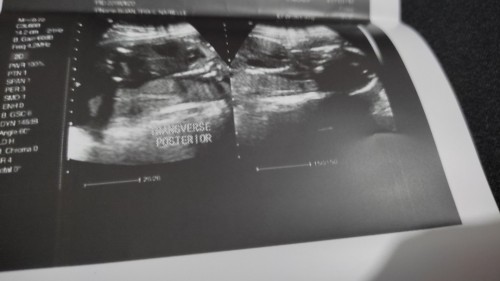

Transverse lie position

Question lang po 20 weeks going 21 weeks ask ko lang po sino yung transverse lie yung position ni baby. Normal po ba sya or iikot pa po si baby. Natatakot po kasi ako baka di na po sya umayos at any tips po sa mga same experience na transverse lie yung position